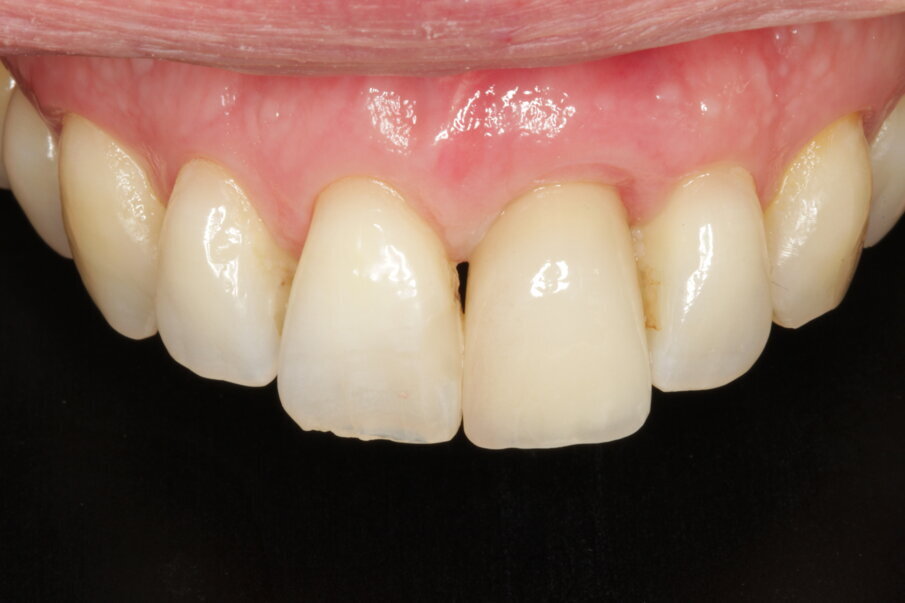

Definitive crown

The author strongly prefers screw-retained devices. Owing to the angulation of the implant, it was necessary to relocate the screw access hole. In CAD, the design for a cobalt-chromium support that copied the gingival profile of the temporary was prepared, and the screw access was brought to the palatal aspect (Fig. 37). The file was sent to the Arc solutions milling centre in Helsingborg in Sweden. High-quality material and CAM production guarantee an excellent outcome in terms of connection and smooth surfaces (Figs. 38–40). The technician layered feldspathic ceramics to obtain the final anatomy and texture. The patient was totally satisfied with the result and did not wish for intervention for the maxillary right central incisor. Minor gingival asymmetries, though evident at high magnification in photography, are not really disturbing when viewed at social distance if all other parameters, like colour, incisal edge, tooth texture, correct proportion of the incisal two-thirds of the tooth and transitions, are respected (Figs. 41–43).